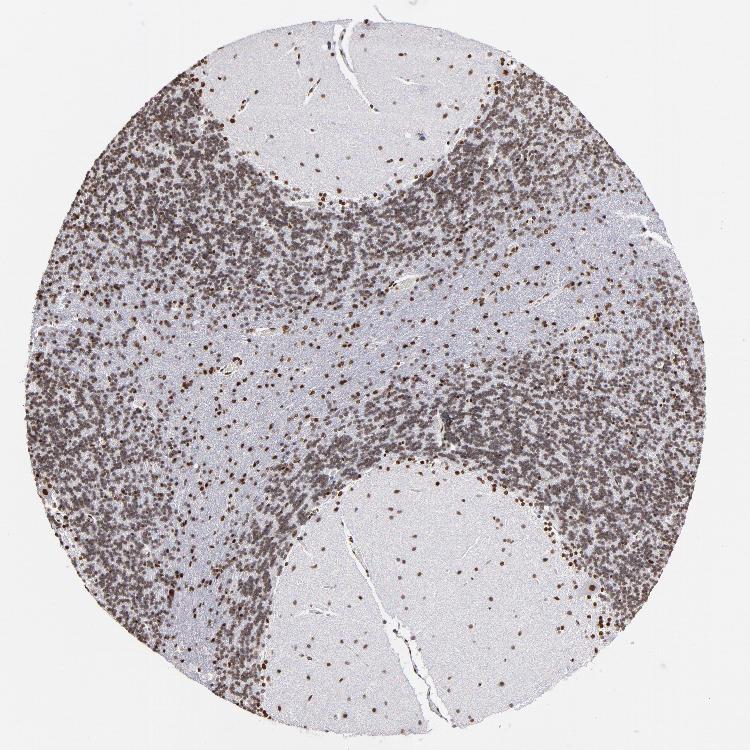

BRAIN CEREBELLUM Show tissue menu

CEREBELLUM - Expression summary

Cells in granular layer: High

Cells in molecular layer: High

Purkinje cells: High

CEREBELLUM - Antibody stainingi

Antibody staining in the annotated cell types in the current human tissue is reported as not detected, low, medium, or high, based on conventional immunohistochemistry profiling in selected tissues. This score is based on the combination of the staining intensity and fraction of stained cells.

Each image is clickable and will lead to virtual microscopy that enables deeper exploration of all samples and also displays staining intensity scores, fraction scores and subcellular localization as well as patient and tissue information for each sample.

Antibody HPA002691Antibody CAB004081

Purkinje cells HighMedium

Cells in granular layer HighLow

Cells in molecular layer HighMedium